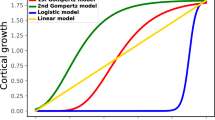

We calculated the local expansion (growth) of each area of the brain by registering each gestational week to the next one on a week by week basis. To determine local growth, we calculated the Jacobian determinant, which represents the local volumetric change (Fig. 1). This spatiotemporal mapping of the lateral hemispheres demonstrates early growth in the frontal, temporal, and parietal opercula, closing the Sylvian fissure from gestational weeks (GW) 23–25. Our analysis demonstrates that focal areas of cortical growth (volumetric expansion) and convergent growth of the opercula close the Sylvian fissure. In later weeks (GW 27–31) differential cortical expansion drives the formation of the major cortical sulci, progressing outward from the central sulcus in the frontal and parietal lobes and inferiorly in the temporal lobe. Although comparable, the left and right hemispheres exhibited asymmetric deformations and gained volume in similar places but at slightly different times, never exceeding 2 weeks of dyscoordination.

Volumetric changes on the lateral hemispheric surface during gestation. Spatiotemporal mapping of the lateral hemispheres. Blue–red color code indicates the Jacobian determinant of the week-to-week co-registration warping, a measure of local volume growth. The Jacobian determinant is normalized for global volume growth, as described in the methods. Postconceptional weeks are indicated. As can be observed, the highest rate of organized growth localizes to the opercula of insula. The first of these “hot zones” is located to the supramarginal gyrus, with the frontal and temporal poles increasing their local expansion at later times. The scale represents the weekly proportional growth (i.e. 1.1 represents a 10% weekly relative expansion). Note that week labels are gestational week (GW).